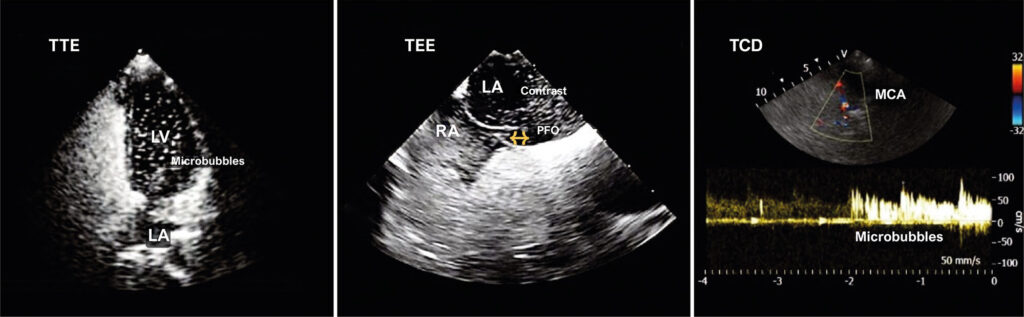

This review article explores the combined use of Transcranial Doppler (TCD) with transthoracic (TTE) and transesophageal (TEE) echocardiography to investigate Patent Foramen Ovale (PFO), a condition found in approximately 25-27% of the adult population. PFO is a remnant of fetal circulation and the most common cause of interatrial shunt. It is associated with clinical complications such as platypnea-orthodeoxia syndrome, obstructive sleep apnea, migraine, and stroke.

PFO assessment is generally performed using TTE and TEE, but TCD, a highly sensitive and less used method, is also important. TCD indirectly detects shunts in awake patients and uses the microembolic signal (MES) grading score to classify shunt severity. This technique involves injecting a contrast solution into the antecubital vein during the Valsalva maneuver to detect intracardiac shunt by observing microbubble appearance in the first cardiac cycles.

The case report illustrates the effectiveness of TCD in the initial screening of a patient with suspected PFO using TTE, TCD and TEE. The conclusion highlights that TCD is a crucial diagnostic tool, particularly relevant for the therapeutic management of patients with cryptogenic stroke. Several scientific publications are referenced, providing a theoretical foundation for the combined use of TCD, TTE, and TEE in PFO investigation.